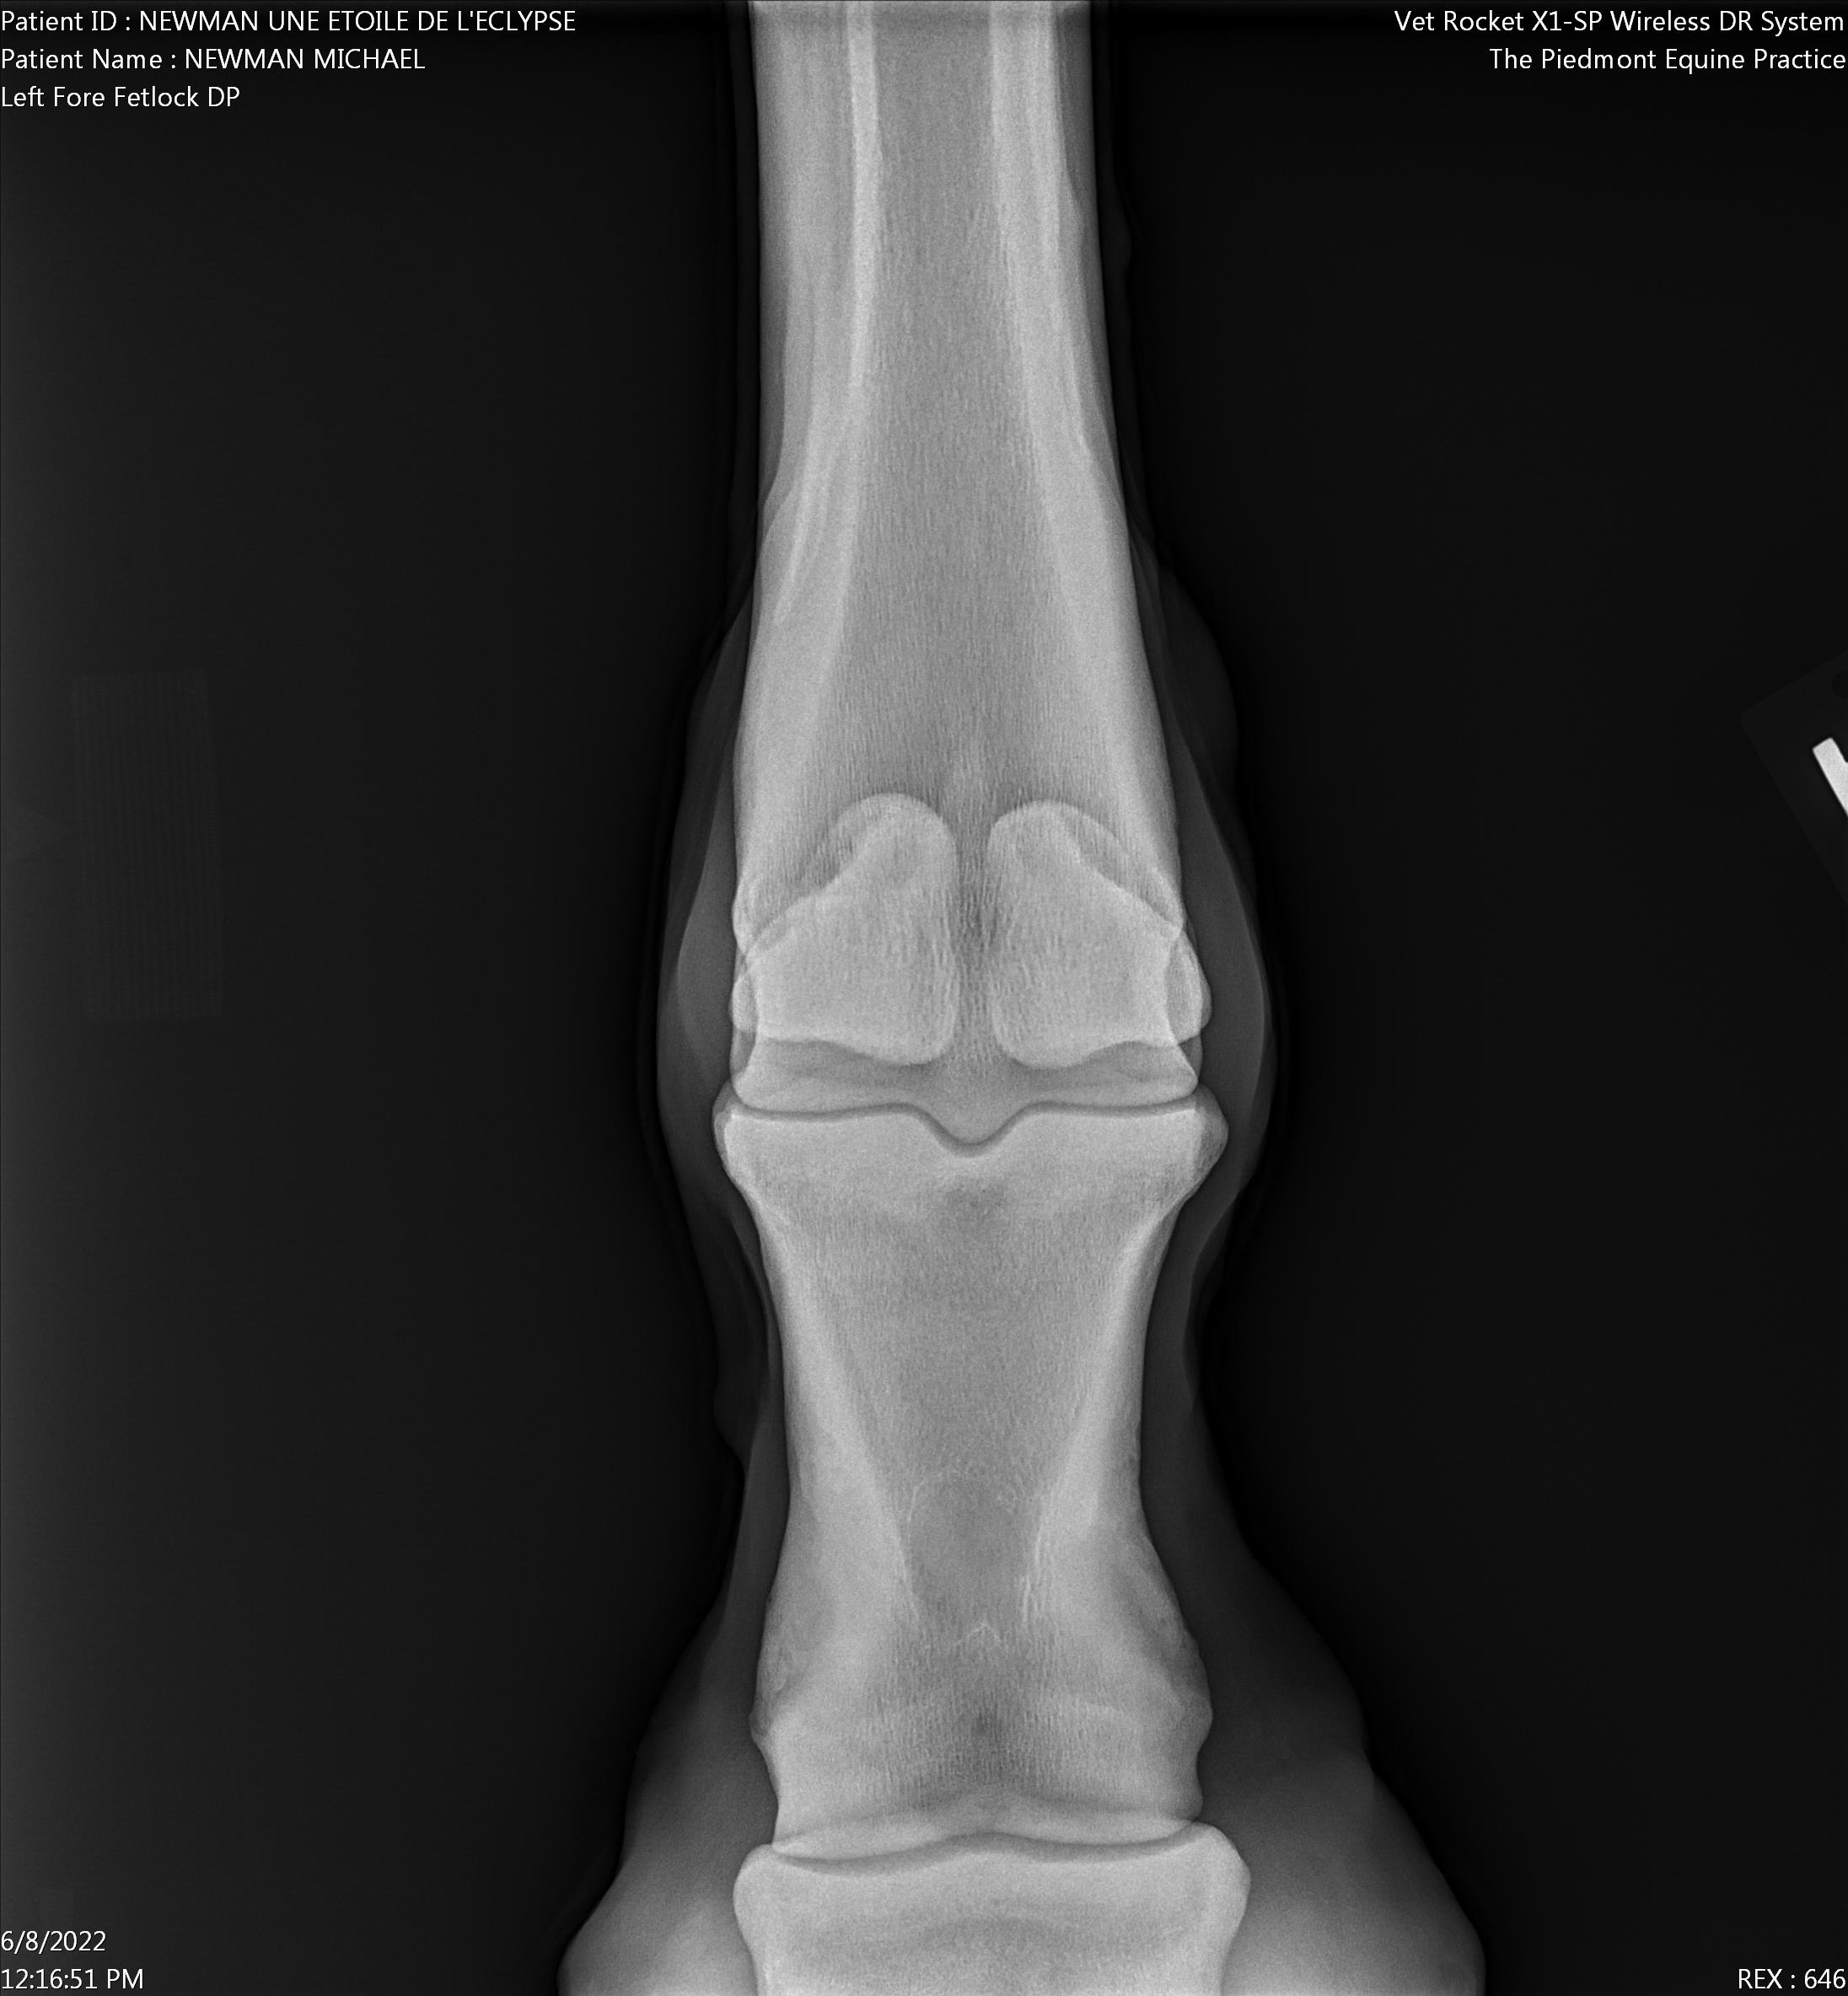

A prepurchase exam was held with with Dr. Davis of piedmont.vet (540) 364-4950 on June 8th at 10 AM.

Basic summary the horse is in remarkably good condition for the age and history. She might not be a candidate for high level dressage, should be ridden more on the straight rather than in the ring. Some minor lameness RT hind hock and RT coffin found, a 1 out of 5. Dr. Davis's overview was that the only surprise in this exam was how good shape she was in for her age and history. Dr. Davis says that several years of hunting with Norfolk should be expected.

Left Fore Fetlock DP